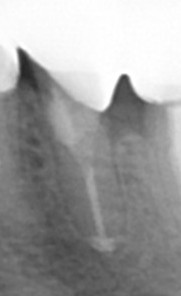

近心の根管壁はパーフォレーションを起こしていたのでMTAにて処置。

【根充 病巣にもMTAが入っている 近心の根管壁はMTA】

【2年後】

近心のパーフォレーション部も治癒。根尖にあった病巣も影が消失。骨が再生した。